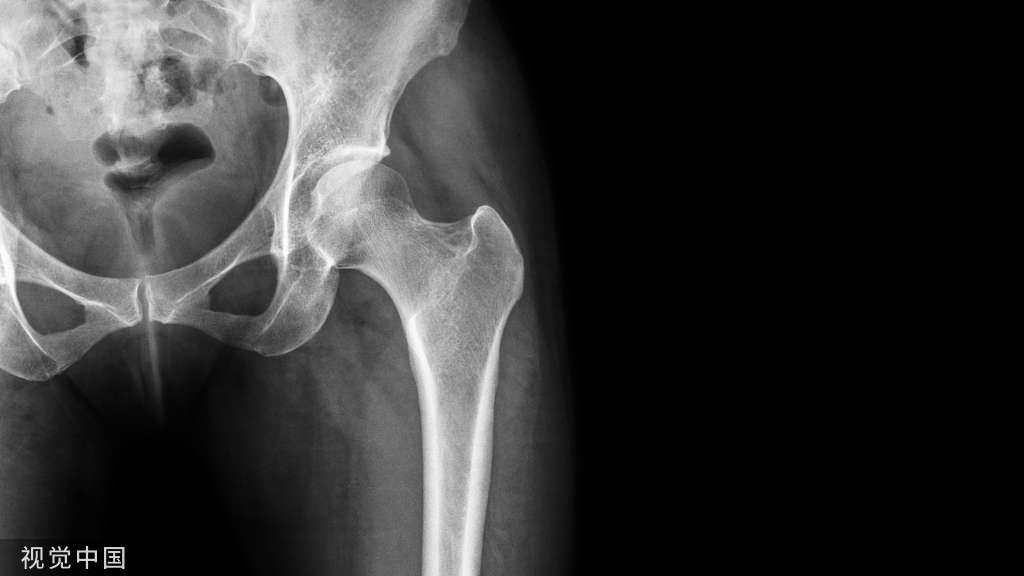

王会余 男  65岁

软骨剥脱